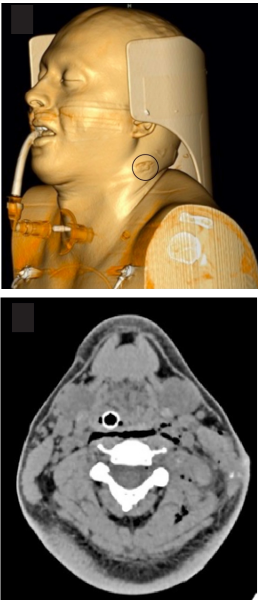

Paciente masculino de 31 años, sin antecedentes patológicos, quien ingresó a una institución de nivel II de atención con una herida por aparente proyectil de arma de fuego sobre el nivel II izquierdo del cuello, asociado a un hematoma contenido, no expansible o pulsátil, sin soplo o frémito, asociado a una equimosis en la región II del lado derecho del cuello. El equipo médico consideró una herida transcervical, aseguró la vía área y lo remitió a nuestra institución de IV nivel. El paciente ingresó estable hemodinámicamente, sin progresión del hematoma y con un estado neurológico no valorable por el estado de sedación.

Por tratarse de un trauma cervical con aparente trayectoria transcervical, en un paciente estable hemodinámicamente, con un signo de sospecha de lesión vascular, e imposibilidad de valoración sintomática por la sedación e intubación orotraqueal, se decidió realizar una angiotomografía de cuello donde reportaron leve enfisema retrofaríngeo, laríngeo y en planos musculares (Figura 1). La tomografía descartó trayecto transcervical, lesión vascular, ósea, nerviosa o de órganos y se identificó un proyectil de caucho (proyectil de energía cinética) alojado en masa muscular paravertebral, con proximidad al musculo elevador de la escapula del lado izquierdo.

El paciente fue interpretado inicialmente como un trauma transcervical porque, además de la herida penetrante en un lado del cuello, exhibía una equimosis contralateral. La presencia de un hematoma estable generó la indicación de la angiotomografía. Posteriormente se aclaró que ese segundo hallazgo no correspondía al mismo traumatismo. Adicionalmente, ante un proyectil alojado en los planos musculares, que no atravesaba la línea media, es probable que el enfisema retrofaríngeo se debiera a una intubación traumática o a la introducción de gas por el mismo proyectil.